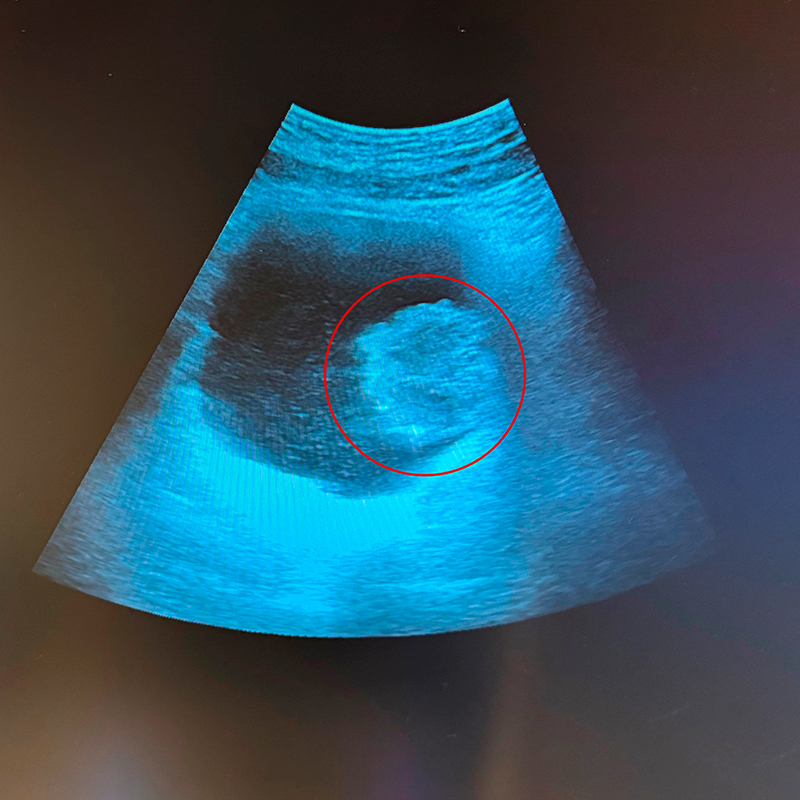

Evaluarea anamnestică a pacientului, urmată de o evaluare imagistică ecografică cu vezica urinară în repleție (plină), a identificat prezența unei tumori vezicale voluminoase, situată pe peretele lateral stâng.

Imaginea 1. Examinare ecografică – tumoră vezicală situată pe peretele lateral stâng al vezicii urinare

Stadializarea preoperatorie prin CT, care a confirmat leziunea vezicală, a fost urmată de o intervenție chirurgicală minim invazivă de rezecție endoscopică a formațiunii identificate (îndepărtarea tumorii folosind un instrument subțire, sub control video, fără incizie externă).